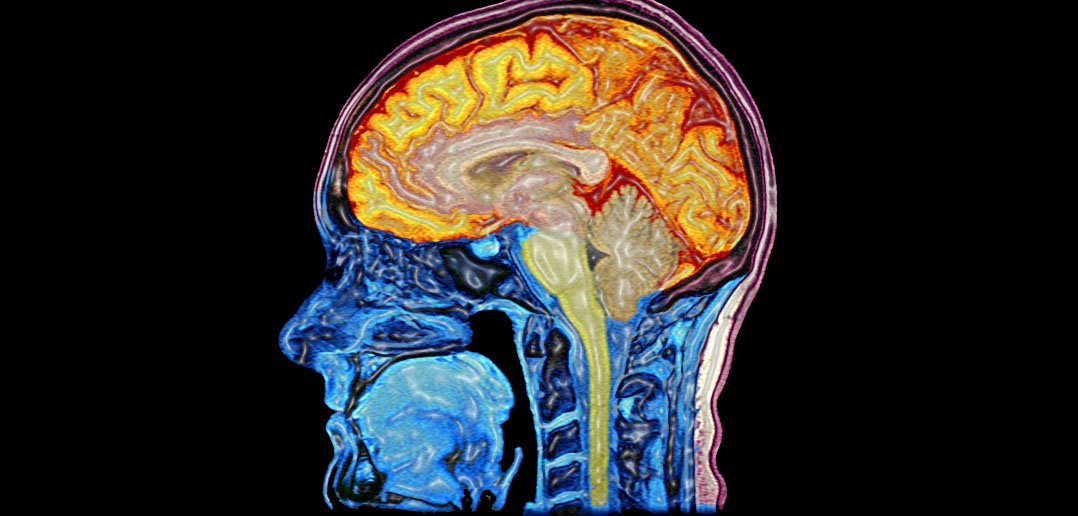

ESA - MRI Brain Scan

www.esa.int

www.esa.int

mri brain scan alzheimer using space imaging human software scans wikipedia identifying esa researchers hypothalamus applications pillars medical wiki thalamus